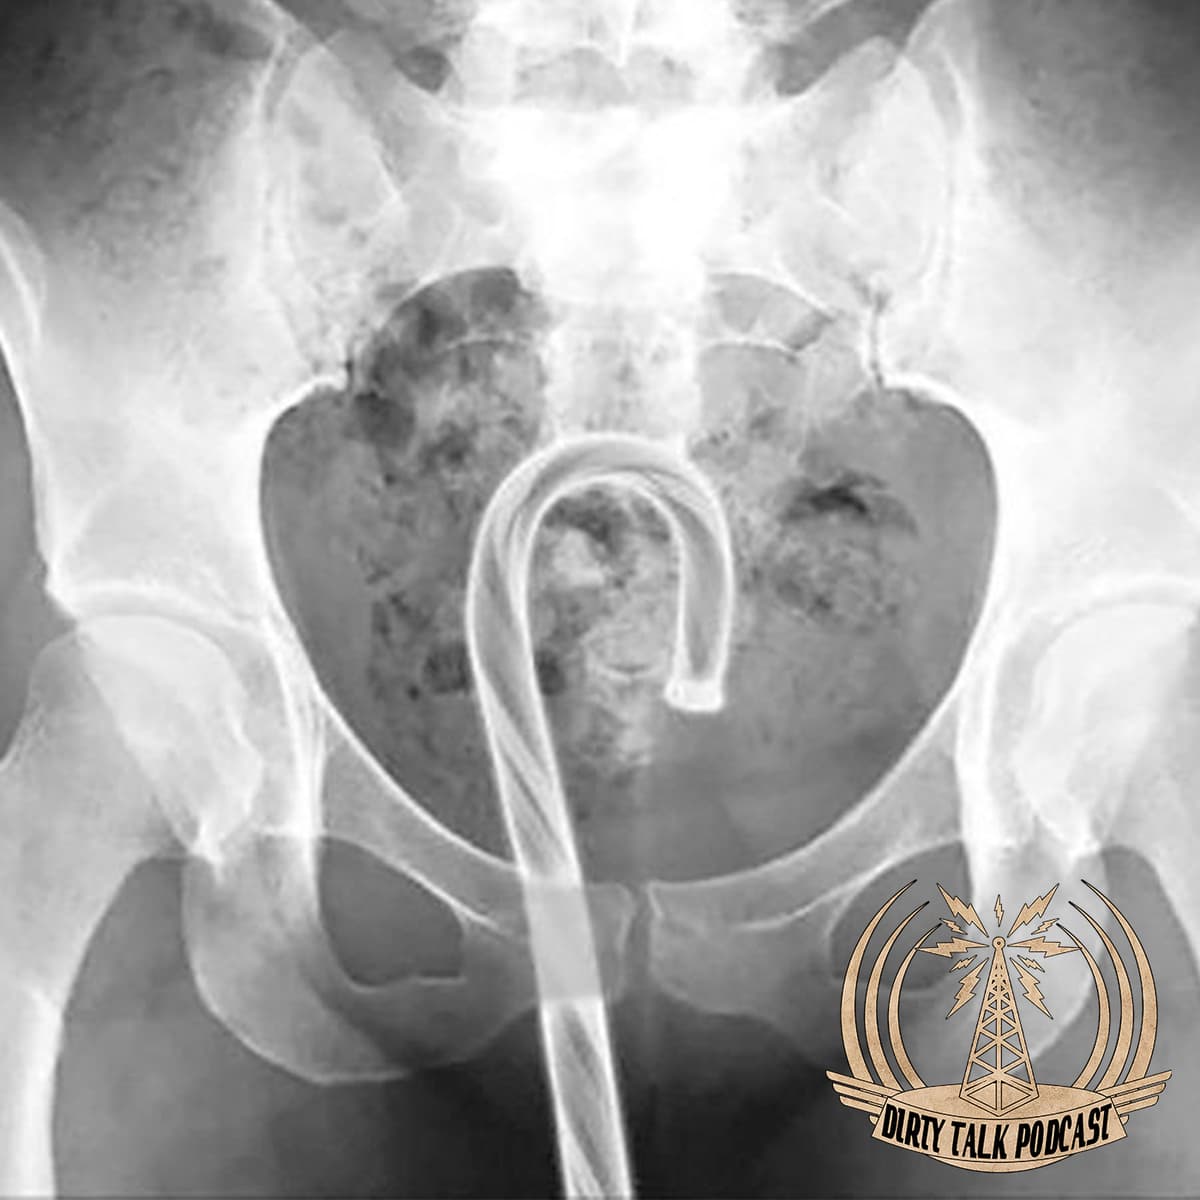

What was lodged inside of us in the past year, who can only mate with a quarter of their species, why are bees better than dogs, when injecting spinal cocaine how should you be prepared, and how can you turn … Continued